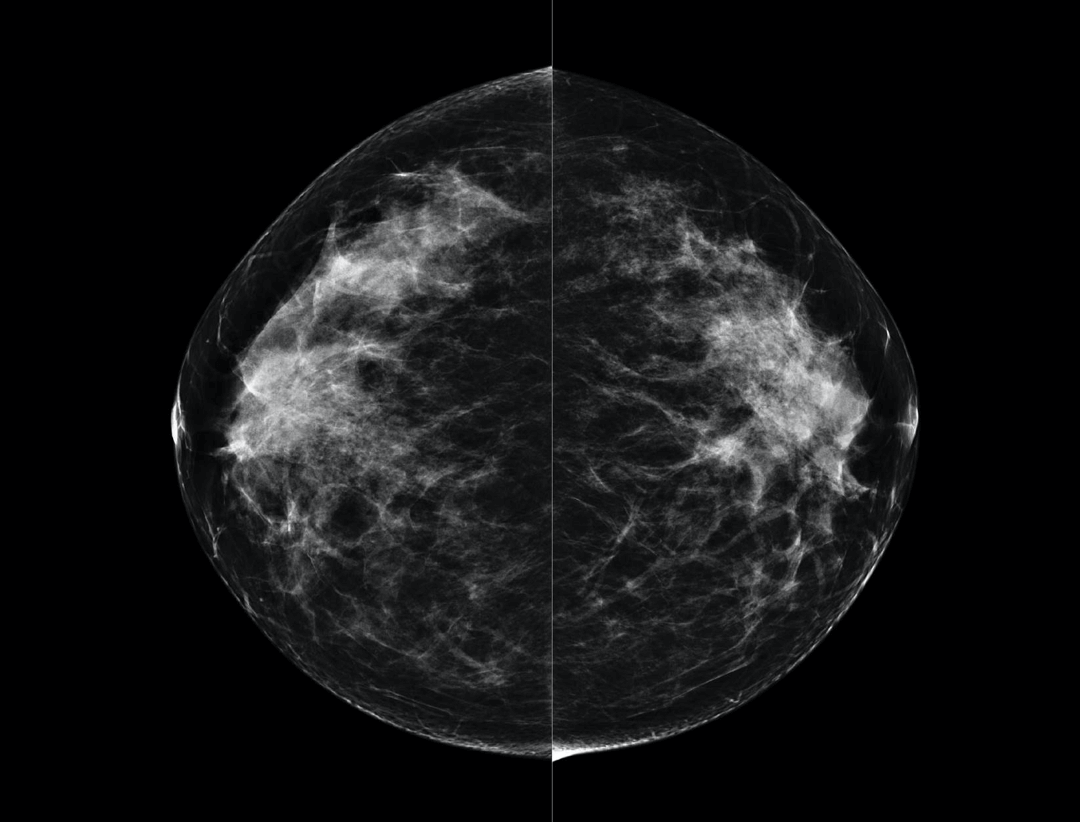

Large coverage amorphous-silicon (a-Si) flat panel detector featuring an optimized active matrix array provides high spatial resolution and high image acquisition speed at a lower dose.

High performance tungsten target X-ray tube offers high resolution image for both dense and fatty breast densities.

Intelligntly detects breast density and thickness, then auto selects the appropriate filter combination.